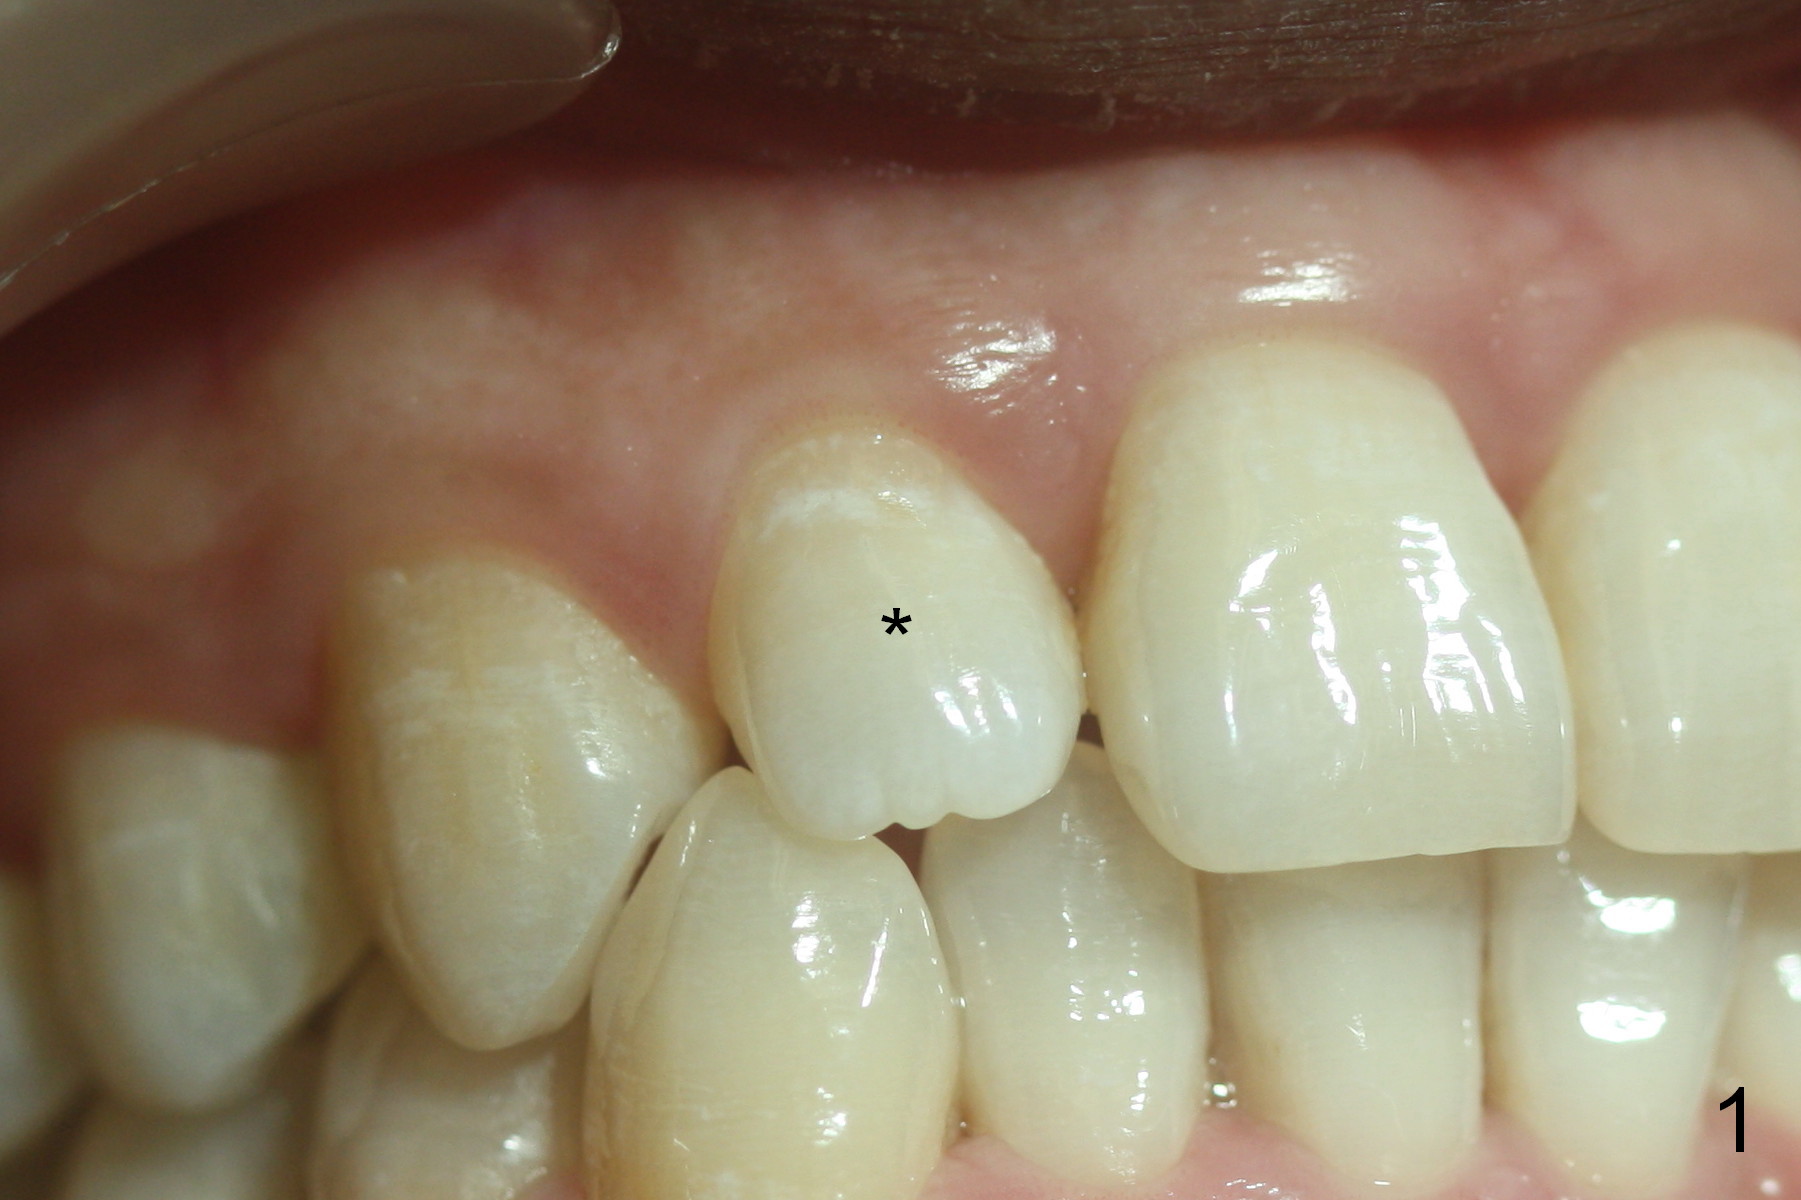

A 36-year-old man has 2 small, congenitally deformed lateral incisors (peg laterals, Fig.1,2 *). After discussion, we choose porcelain veneers for cosmetic makeup. The teeth need minor shaving (Fig.3,4); right colors are being selected with a shade guide (Fig.4: G). The shaving is so conservative that there is no pain during the procedure and there is no need to make temporary veneers. One to 2 weeks later, porcelain veneers are cemented (Fig.5,6). The patient is satisfied.